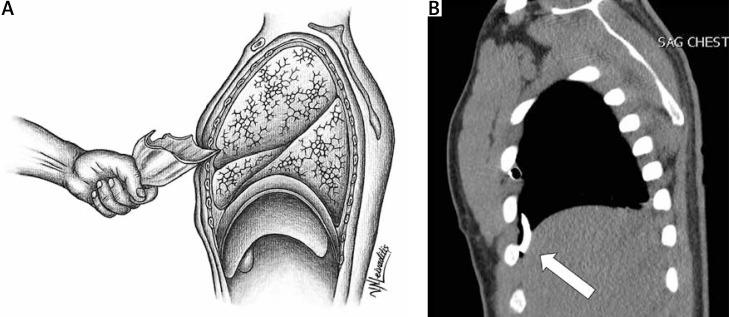

Retained broken beer bottle following penetrating thoracic trauma: challenges in diagnosis and treatment dilemma.

https://cdn.ncbi.nlm.nih.gov/pmc/blobs/bd3b/11523479/d1dc3a0e12eb/KITP-21-54865-g001.jpg